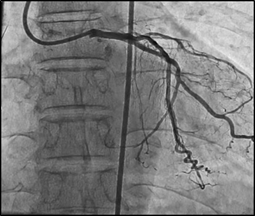

Figure 1: Successful PCI of Left

Therapeutic Intervention: Given the complexity of the bifurcation lesion and the imperative to preserve the side branch, the Culottes technique was skillfully employed for the percutaneous coronary intervention (PCI). Using an XB3.5 guide catheter, precise wiring and predilation were performed on both the Left Anterior Descending (LAD) and Left Circumflex (LCX) arteries. A strategic sequence of steps ensued, the stent was initially deployed in the angulated side branch (LCX) with simultaneous wire jailing of LAD. Subsequently, the LCX wire was withdrawn, LAD was rewired, and careful dilation of struts facing the LAD ostium was executed. The deployment of the stent from the left main to LAD followed, accompanied by the first post-dilation (POT). The LCX was then rewired through the struts connecting the left main to LCX and left main to LAD. Concurrent balloon inflation was meticulously conducted, culminating in the final POT. Upon completing the final POT, the balloon was tactfully pulled back to allow partial placement in the aorta, facilitating the flaring of the stent. This meticulous and intricate intervention protocol effectively addressed the challenging bifurcation lesion while safeguarding the side branch.